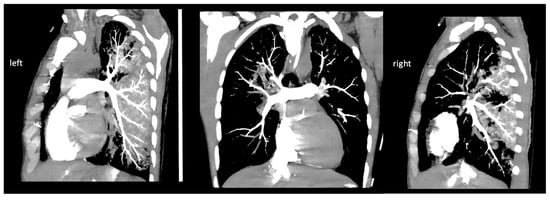

| 21:34 | cranial, thoracic, and abdominal CT scan; pulmonary CT angiography to rule out acute aortic dissection and acute pulmonary embolism | |